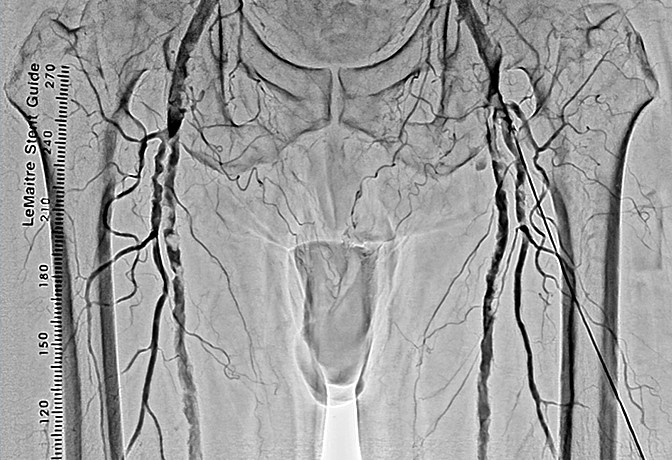

- 首先,双腿能拍到同一画面中这一点很好。还有手术中,由于能够区别使用纵向16英寸、横向16英寸,例如,希望拍摄双腿全长时可以横着跟踪拍摄。采用DSA时,由于迄今为止也都不得不分几次进行拍摄,因此需要患者承担造影剂的负担,而我认为拍摄次数减少对于患者来说是大有裨益的。但即便如此,如果不能拍摄冠状动脉就没有意义了,然而这台机器对于冠状动脉也可以正常拍摄。在搭桥等过程中,无需跟踪也可以将希望看到的区域全部拍摄出来,因此画面不会发生抖动,容易拍摄。

另外,正如曾我医生所说的那样,在跟踪拍摄时,通过将16英寸一侧置于横向,可以一次拍摄到双下肢的全部长度,导管床也在纵向的移动行程长,仅通过移动导管床就可以拍摄到足尖的位置。

- SCORE Chase真的很不错。即使导管床横向移动也能将血管图像自动连接起来,真是非常厉害。为什么之前没有呢?所有来云顶国际医院参观的人都觉得很震惊。

- 曾我

- 大家都说“这个真好啊”。一直以来都是通过手动的方式将血管的图像连接起来的,由于图像间有亮度差,因此非常费功夫。多亏有了SCORE Chase,不需要再这样做了。它会对图像进行校正,瞬间将图像自动连接起来,真的非常方便。